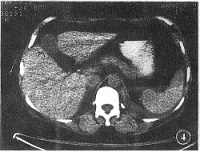

腹腔横断面(通过网膜孔)